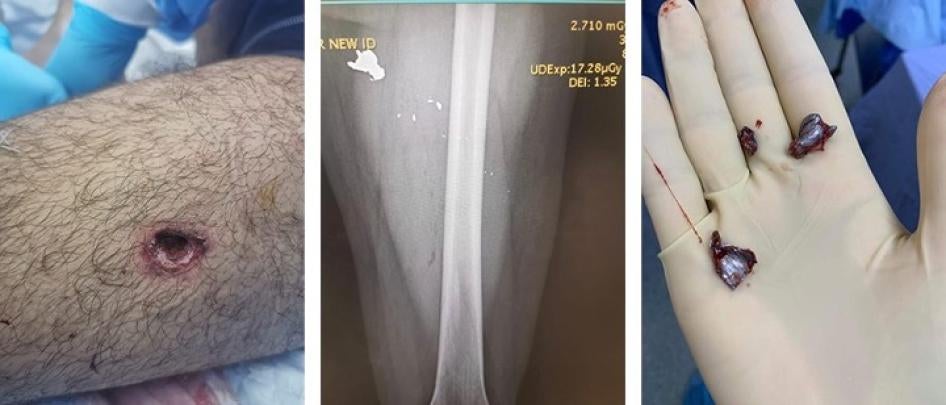

قال متظاهر يُدعى عمر، طلب مثل آخرين عدم الكشف عن شهرته لدواعي حمايته، إنّه، في حوالي الساعة 7:30 مساء، كان يتظاهر سلميا أمام فندق لو غراي وزقاق مجاور على "جبهات" التظاهر. سمع إطلاق نار ورأى شخصين يطلقان النار على المتظاهرين، وأطلق أحدهما كان يرتدي سروال جينز وتيشرت سوداء، الرصاص من مسدس على عمر الذي اختبأ وراء حائط.

عندما هدأ إطلاق النار، كما قال عمر، ترك مخبأه وأطلق عليه الشخص نفسه النار من مسافة أقلّ من عشرة أمتار، فأصابه في أعلى فخذه الأيسر. قال: "عندما أصابني في البداية، لم أشعر بذلك. نظرت إلى رجلي ورأيتها تنزف. أردت الانسحاب، لكنّني وقعت فور أن خطوت خطوتين".

راجعت هيومن رايتس ووتش السجلّات الطبية لعمر في 8 أغسطس/آب، بما فيها صور الأشعّة السينية التي أظهرت ثلاث شظايا كبيرة من الرصاص وشظايا عديدة أصغر في رجله اليسرى. قال: "لحسن الحظ، لم تصل الرصاصة إلى عظمي. كانت قريبة من الشريان، لكنّها بالكاد لم تلامسه".

أطلقت القوات الأمنية رصاصة على عمر فأصابت أعلى فخذه الأيسر. الصورة على اليسار تظهر جرح دخول الرصاصة. تُظهر الأشعة السينية ثلاث شظايا رصاصة كبيرة وعدة شظايا أصغر في ساقه اليسرى، والصورة على اليمين تُظهر الشظايا المستخرجة من ساقه.  © 2020 تقدمة عمر